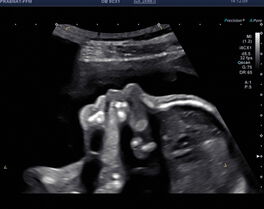

Fetale Echokardiografie

Bei gezielter Fragestellung wird das Herz des Kindes noch fokussierter beurteilt. Hierbei werden sämtliche zu- und abführende Gefäße genau beurteilt und in Relation zu einander gestellt.

Hiermit können wir Ihnen sagen, ob das kindliche Herz sonografisch gesund ist. Zeigen sich doch einmal Auffälligkeiten, dann können mögliche Herzfehler genau beurteilt werden und Ihrem Kind und Ihnen schon jetzt geholfen werden.